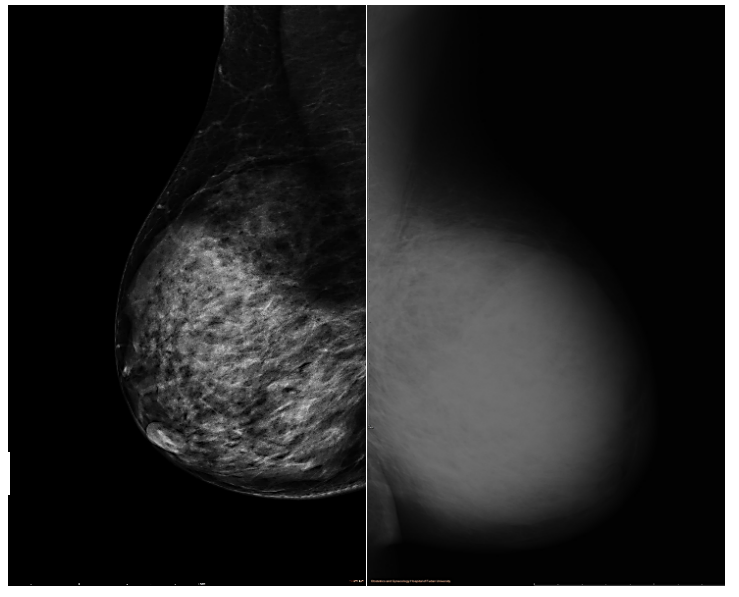

钼靶提示左乳弥漫性增高密度影,边界不清,恶性可能。双腋下未见肿大的淋巴结。BI-RADS 5(图2)。

图2.钼靶(左乳弥漫性增高密度影)